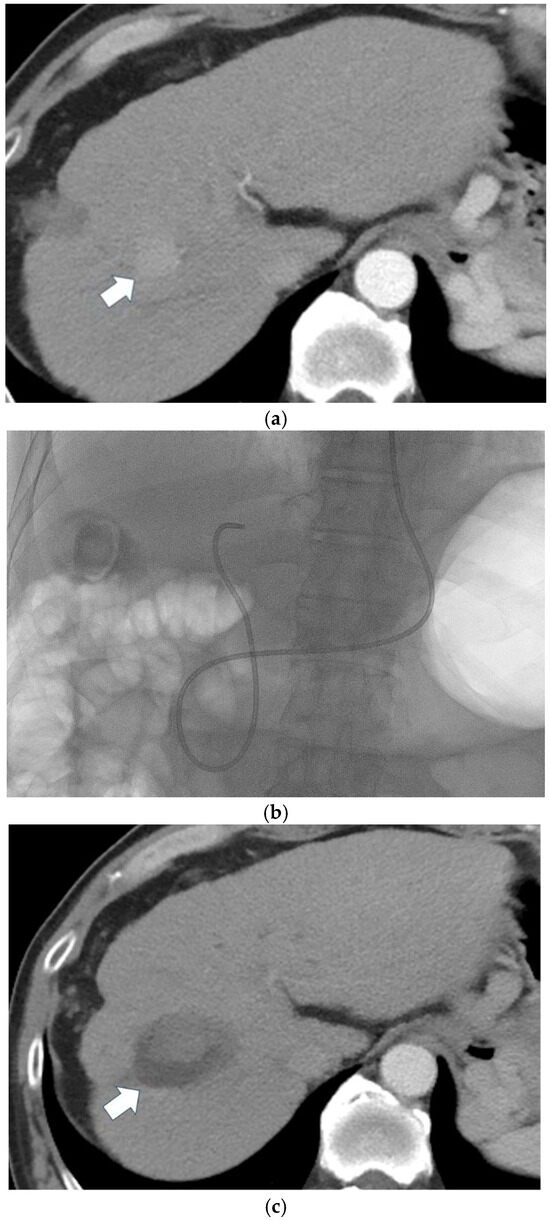

Hepatocellular carcinoma (HCC) is the most frequently observed primary malignant liver tumor and is a major cause of worldwide mortality. Despite the advent of screening programs for patients with known risk factors, a substantial number of patients are ineligible for curative surgery at presentation. Thus, locoregional treatments now hold a pivotal role in HCC management; trans-arterial chemoembolization, percutaneous ablation and more recently selective internal radiation therapy are often the first-line treatments for selected stages of HCC or serve as a bridge to liver transplantation.